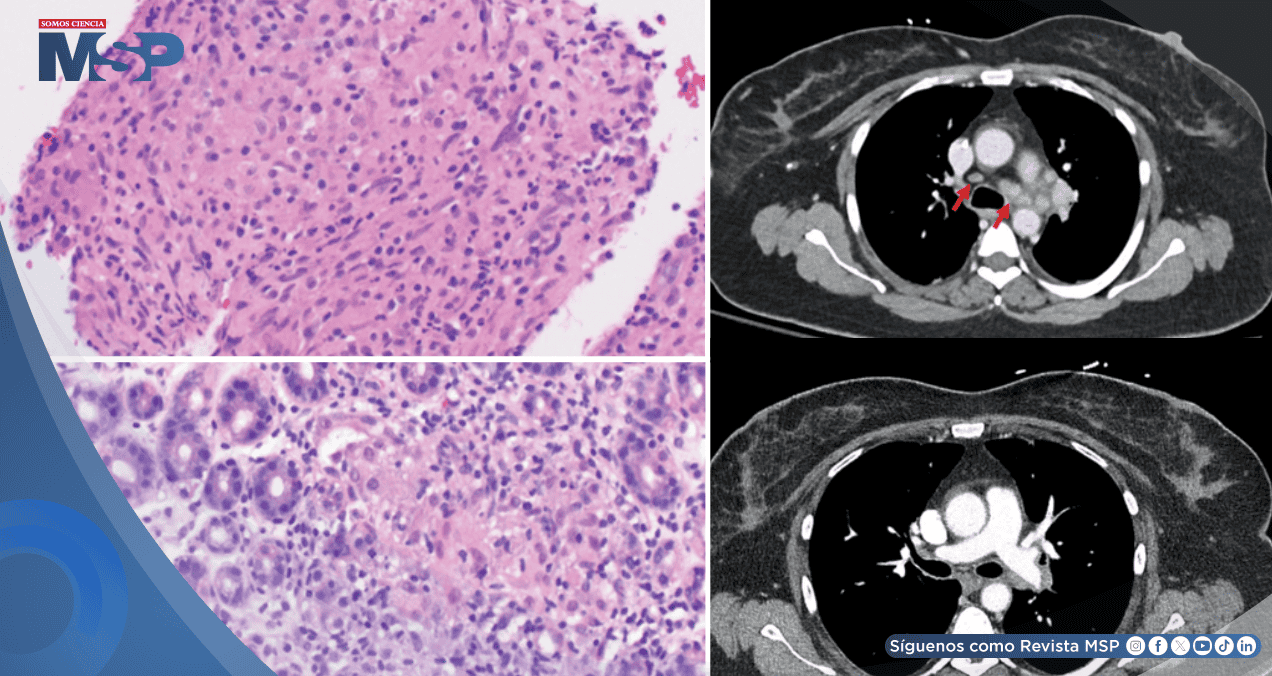

Mientras una tomografía abdominal resultaba normal, un estudio de imágenes del tórax arrojó un hallazgo crítico e inesperado: la presencia de múltiples ganglios linfáticos significativamente agrandados en el mediastino y las regiones hiliares pulmonares.

Este descubrimiento generó inicialmente una alta sospecha de progresión metastásica de la enfermedad oncológica.

Los debilitantes síntomas gastrointestinales se resolvieron por completo y, en un seguimiento imagenológico posterior, se documentó una mejoría muy significativa en el tamaño de los ganglios linfáticos mediastínicos e hiliares, confirmando la naturaleza inflamatoria y no maligna del proceso.